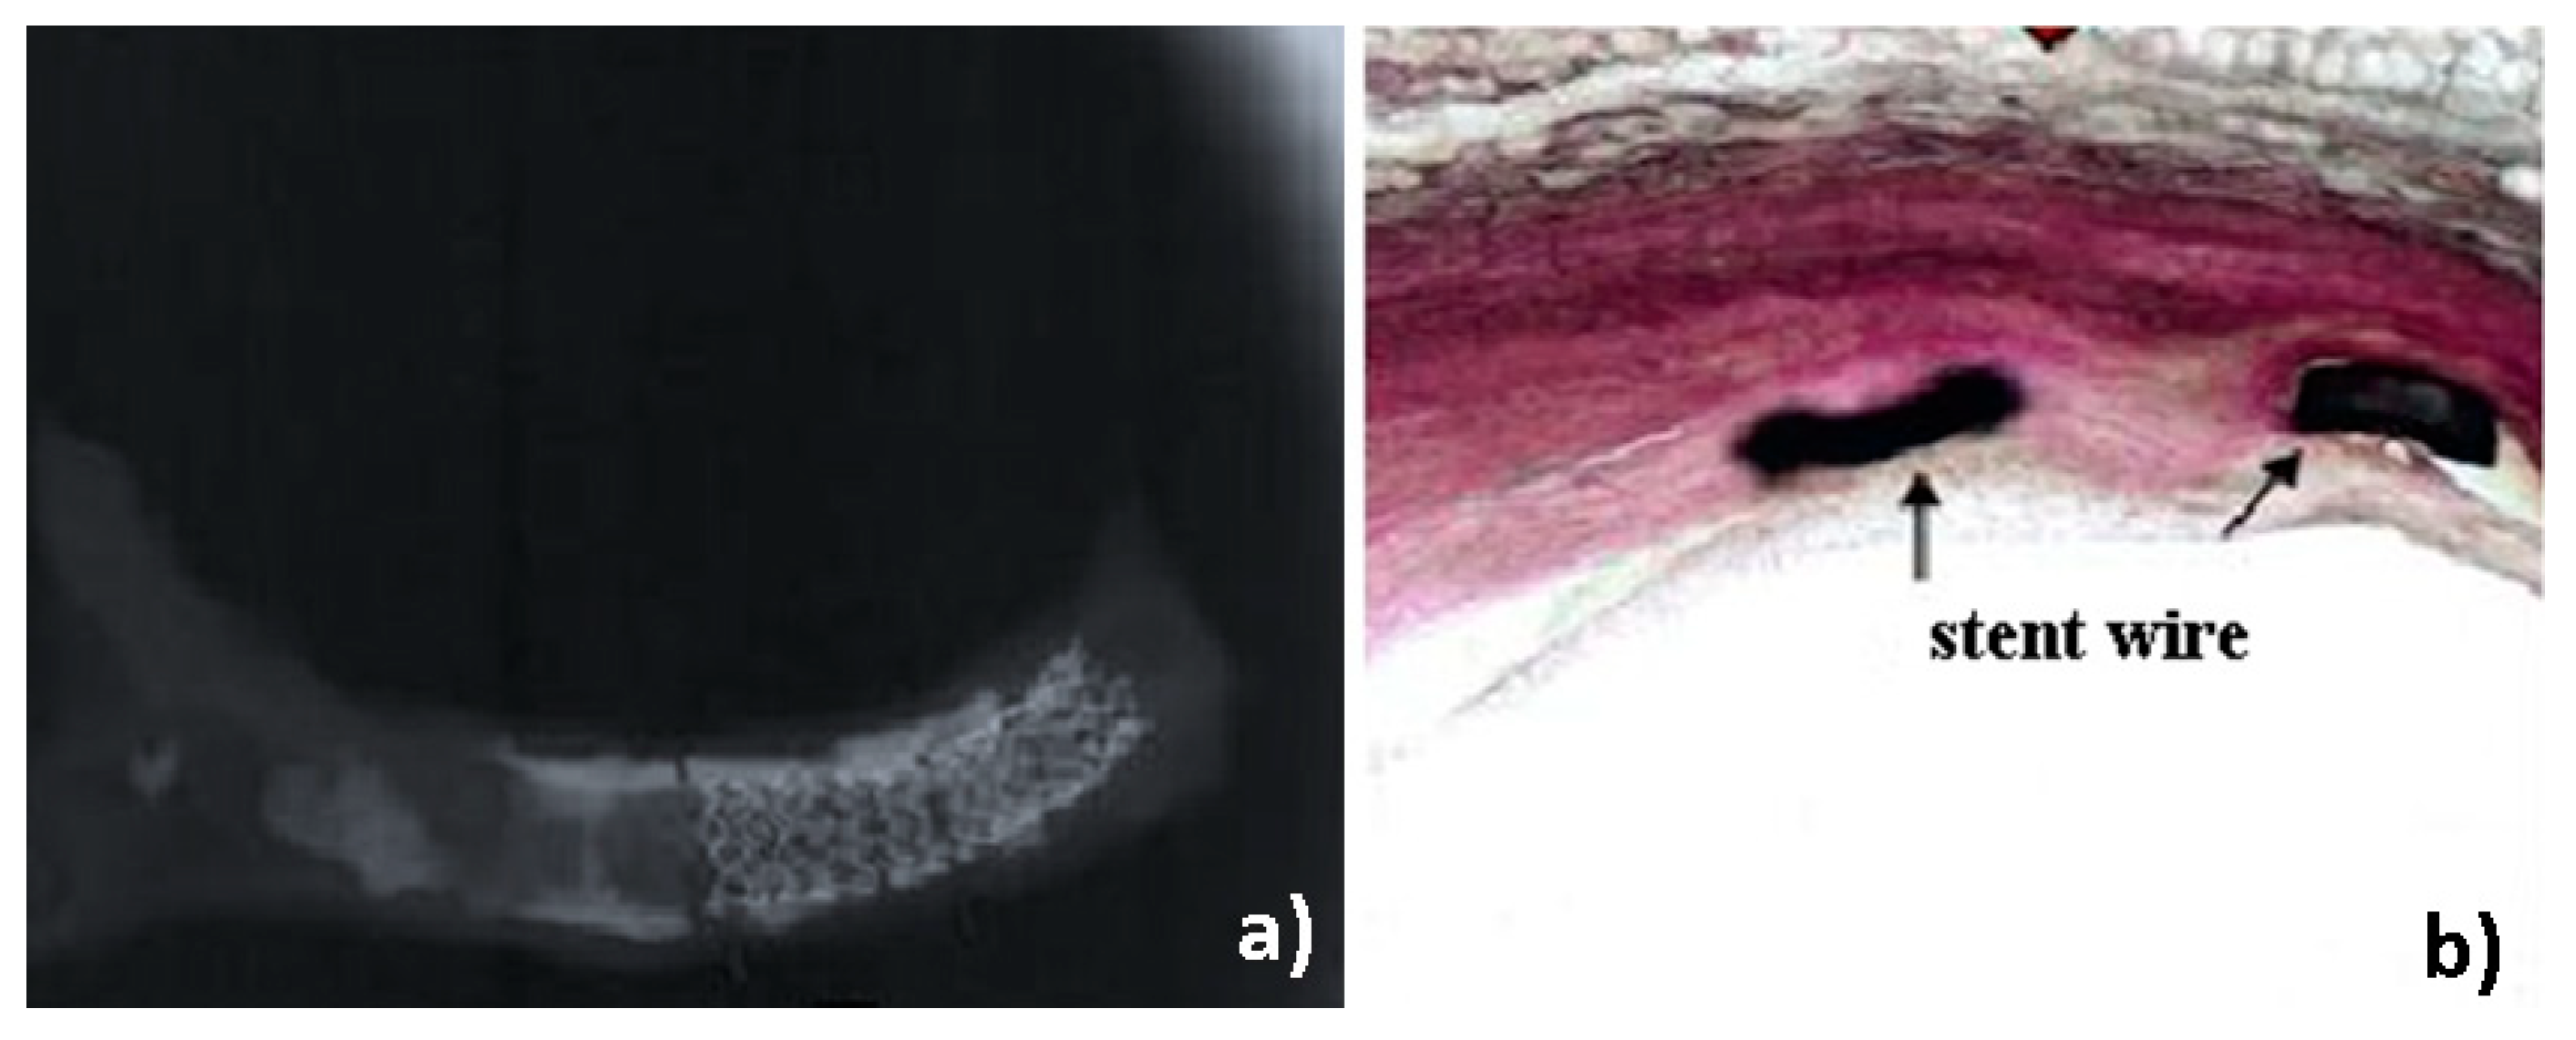

Radiography of one sample (P11) showed diffuse calcification surrounding a stent (Figure 11a) and associated cross section show a reendothelization of the stent struts with absence of in-stent restenosis (ISR) (Figure 11b).

Figure 11.

(a) Radiography and (b) associated cross section of sample P11.